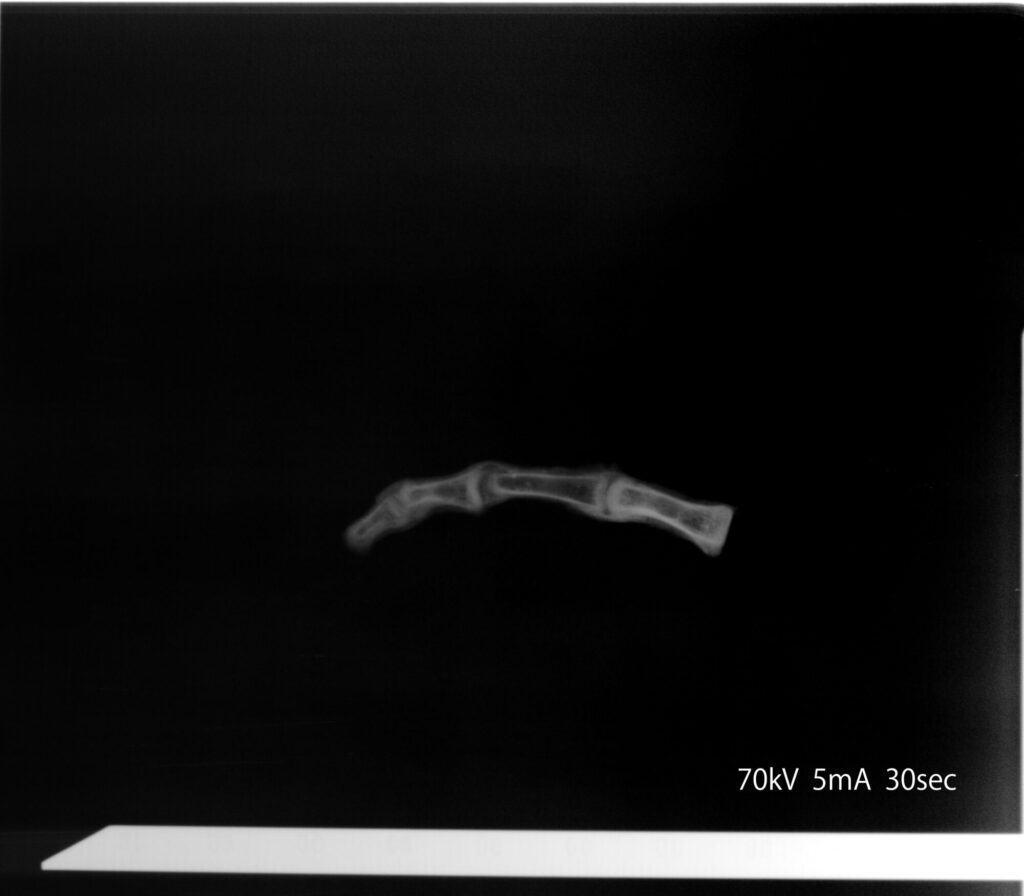

まずはこちらの画像をご覧いただきたい。

これはパレオ・ラボで撮影した指骨のX線画像である。通常であれば足の指骨は爪先の末節骨から順に中節骨、基節骨の3つの骨で形成されている。しかしこの指骨には、ヒトより関節が1つ多く、4つあるのがおわかりいただけるだろうか。

このことについて担当者は、関節に不自然な“浮き”があること、そして爪先部分を欠いた中節骨から始まっていることから、「複数種の骨をつなぎ合わせて作成されたもの」だと推測している。事実、断面を見せてもらうと、樹脂だろうか。黄色の液体を注入したような痕跡も残されていた。

そこでさらに、「指」の提供者である「X」から見せてもらったナスカ・ミイラの全身のX線画像をみてもらうと、さらに驚くべき事実が浮かび上がってきた。足指のみならず、全身、複数の骨をつなぎ合わせて作られている可能性が高いというのだ。